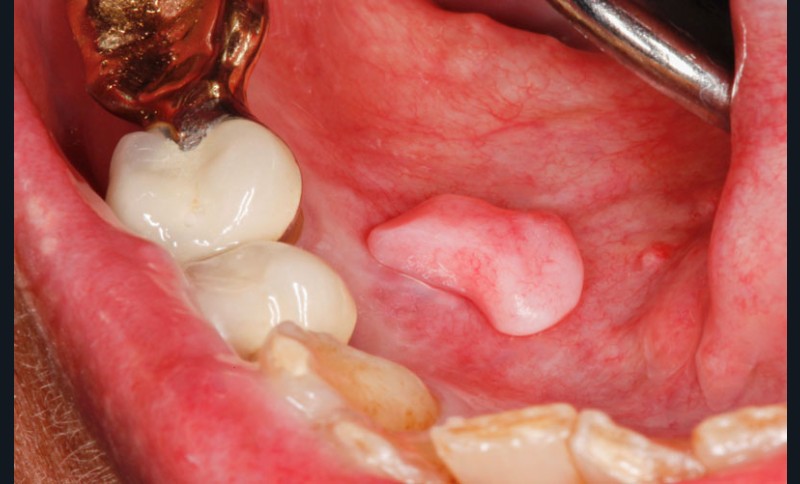

Sur le plancher buccal antérieur droit, on observait une tumeur pédiculée, oblongue, de 9 x 5 x 4 mm, de consistance élastique. Elle implantait au centre du plancher du plancher buccal antérieur droit. Devant ce tableau clinique, il n’était guère possible d’évoquer un diagnostic.

L’examen histopathologique de la pièce d’exérèse a montré qu’il s’agissait d’un nodule revêtu d’un épithélium malpighien, parakératinisé, mince, avec des crêtes épithéliales raccourcies, focalement absentes. Son centre était constitué par du tissu conjonctif fibreux dense, contenant des vaisseaux à paroi fine. On notait la présence en un point d’un petit amas de lymphocytes qui pénétraient les assises épithéliales profondes. Cet aspect était assez caractéristique d’un nodule d’hyperplasie fibro-épithélial de grande taille et de localisation inhabituelle.